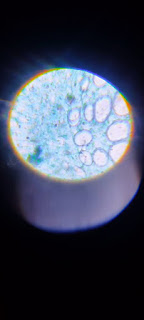

Fotografías del trabajo escolar de 6° grado, ciclo escolar 2022 - 2023

Hola alumnos, colocaremos en esta publicación más fotografías de las actividades con la finalidad de que las podamos emplear en nuestro Proyecto de Español: Elaborar un álbum de recuerdos de la primaria.

También, las imágenes nos servirán para la rendición de cuentas ya que muestran gran parte de las actividades desarrolladas en nuestro grupo, dentro de este ciclo escolar.